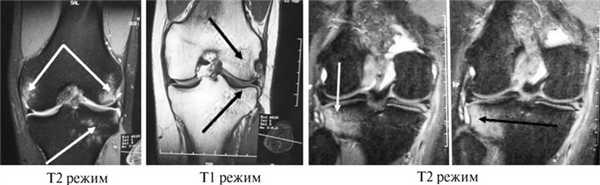

Т1 т2 ви это

Т1 т2 ви это 116 фото